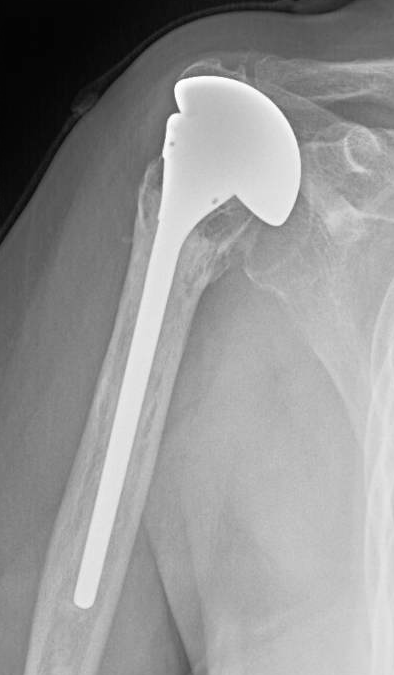

One of the principal indications for a reverse total shoulder arthroplasty is the revision of a failed anatomic arthroplasty. We have had quite a few of these cases recently and wanted to share a few examples with our readers. The problem in each of these cases was cuff / tuberosity deficiency that resulted in superior instability and pseudoparalysis (inability to elevate the arm more than 45 degrees).

As can be seen from some of these cases, revision can be technically difficult, especially if the previous prosthesis had a narrow stem securely cemented into the humeral canal. In these situations we use a 72,000 rpm bur to remove enough cement for the reverse stem. Penetration of the humeral cortex is not uncommon; when this occurs, we apply a wire mesh patch to the inside of the canal prior to cementation and insertion of the humeral prosthesis. It may be necessary to shorten the humeral stem as well. The new prosthesis is cemented in the remainder of the prior cement mantle.